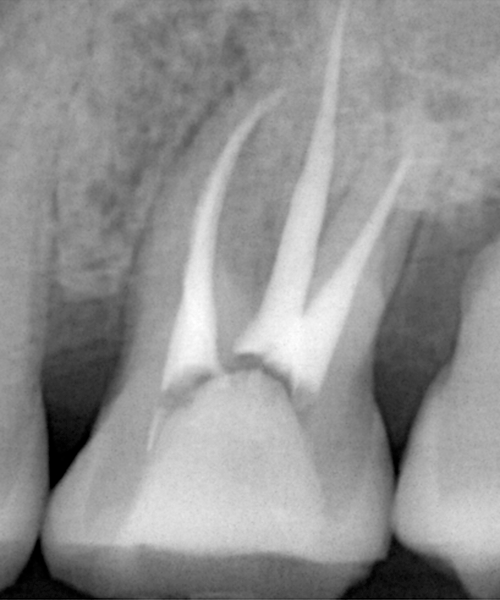

根尖性歯周炎(こんせんせいししゅうえん)

重度の虫歯や歯周病などを放置したために骨の中まで炎症が進行すると、炎症が歯の根の先端まで到達し、周りの骨にまで炎症が波及する「根尖性歯周炎」と呼ばれる状態になります。

また一度根管治療を行なった歯が、根尖性歯周炎となってしまうことも多くみられます。

根管治療後、痛みや炎症などの症状が落ち着いたら、根管内への細菌侵入を防ぐために専用の薬剤で根管を埋める「根管充填」という治療を行います。

根管は人それぞれに形態や本数が異なり、非常に複雑で入り組んだ形状のため精密さが求められます。さらに根の中に唾液や細菌が入り込まないように治療中にも細心の注意が必要になります。早い方は数回で終了しますが、歯の形状や症状の度合いによっては数か月、またはそれ以上かかることもあります。